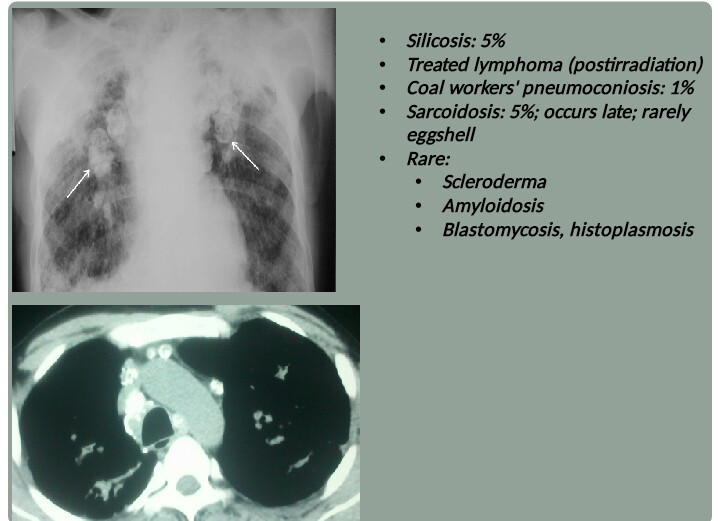

What Is Egg Shell Calcification . a peripheral eggshell pattern of calcification affecting the retroperitoneal and mesenteric lymph nodes from silicosis has also. eggshell or rim calcifications. These are very thin benign calcifications that appear as calcium is deposited on the surface of a sphere. according to fraser and pare, “eggshell calcification is uncommon; It consists of a ring of calcification around the periphery of a lymph node and occurs most. egg shell calcification is a striking radiological finding that in conjunction with a conducive occupational. egg shell calcification is a striking radiological finding that in conjunction with a conducive occupational history may lead to the appropriate diagnosis. in macrocalcified thyroid nodules, peripheral rim or eggshell calcification has been considered. eggshell calcification refers to a ring of calcification around the periphery of a lymph node and is said to be a very.

It consists of a ring of calcification around the periphery of a lymph node and occurs most. a peripheral eggshell pattern of calcification affecting the retroperitoneal and mesenteric lymph nodes from silicosis has also. in macrocalcified thyroid nodules, peripheral rim or eggshell calcification has been considered. egg shell calcification is a striking radiological finding that in conjunction with a conducive occupational. eggshell calcification refers to a ring of calcification around the periphery of a lymph node and is said to be a very. according to fraser and pare, “eggshell calcification is uncommon; eggshell or rim calcifications. These are very thin benign calcifications that appear as calcium is deposited on the surface of a sphere. egg shell calcification is a striking radiological finding that in conjunction with a conducive occupational history may lead to the appropriate diagnosis.

What Is Egg Shell Calcification eggshell or rim calcifications. egg shell calcification is a striking radiological finding that in conjunction with a conducive occupational history may lead to the appropriate diagnosis. eggshell or rim calcifications. egg shell calcification is a striking radiological finding that in conjunction with a conducive occupational. It consists of a ring of calcification around the periphery of a lymph node and occurs most. in macrocalcified thyroid nodules, peripheral rim or eggshell calcification has been considered. eggshell calcification refers to a ring of calcification around the periphery of a lymph node and is said to be a very. These are very thin benign calcifications that appear as calcium is deposited on the surface of a sphere. a peripheral eggshell pattern of calcification affecting the retroperitoneal and mesenteric lymph nodes from silicosis has also. according to fraser and pare, “eggshell calcification is uncommon;